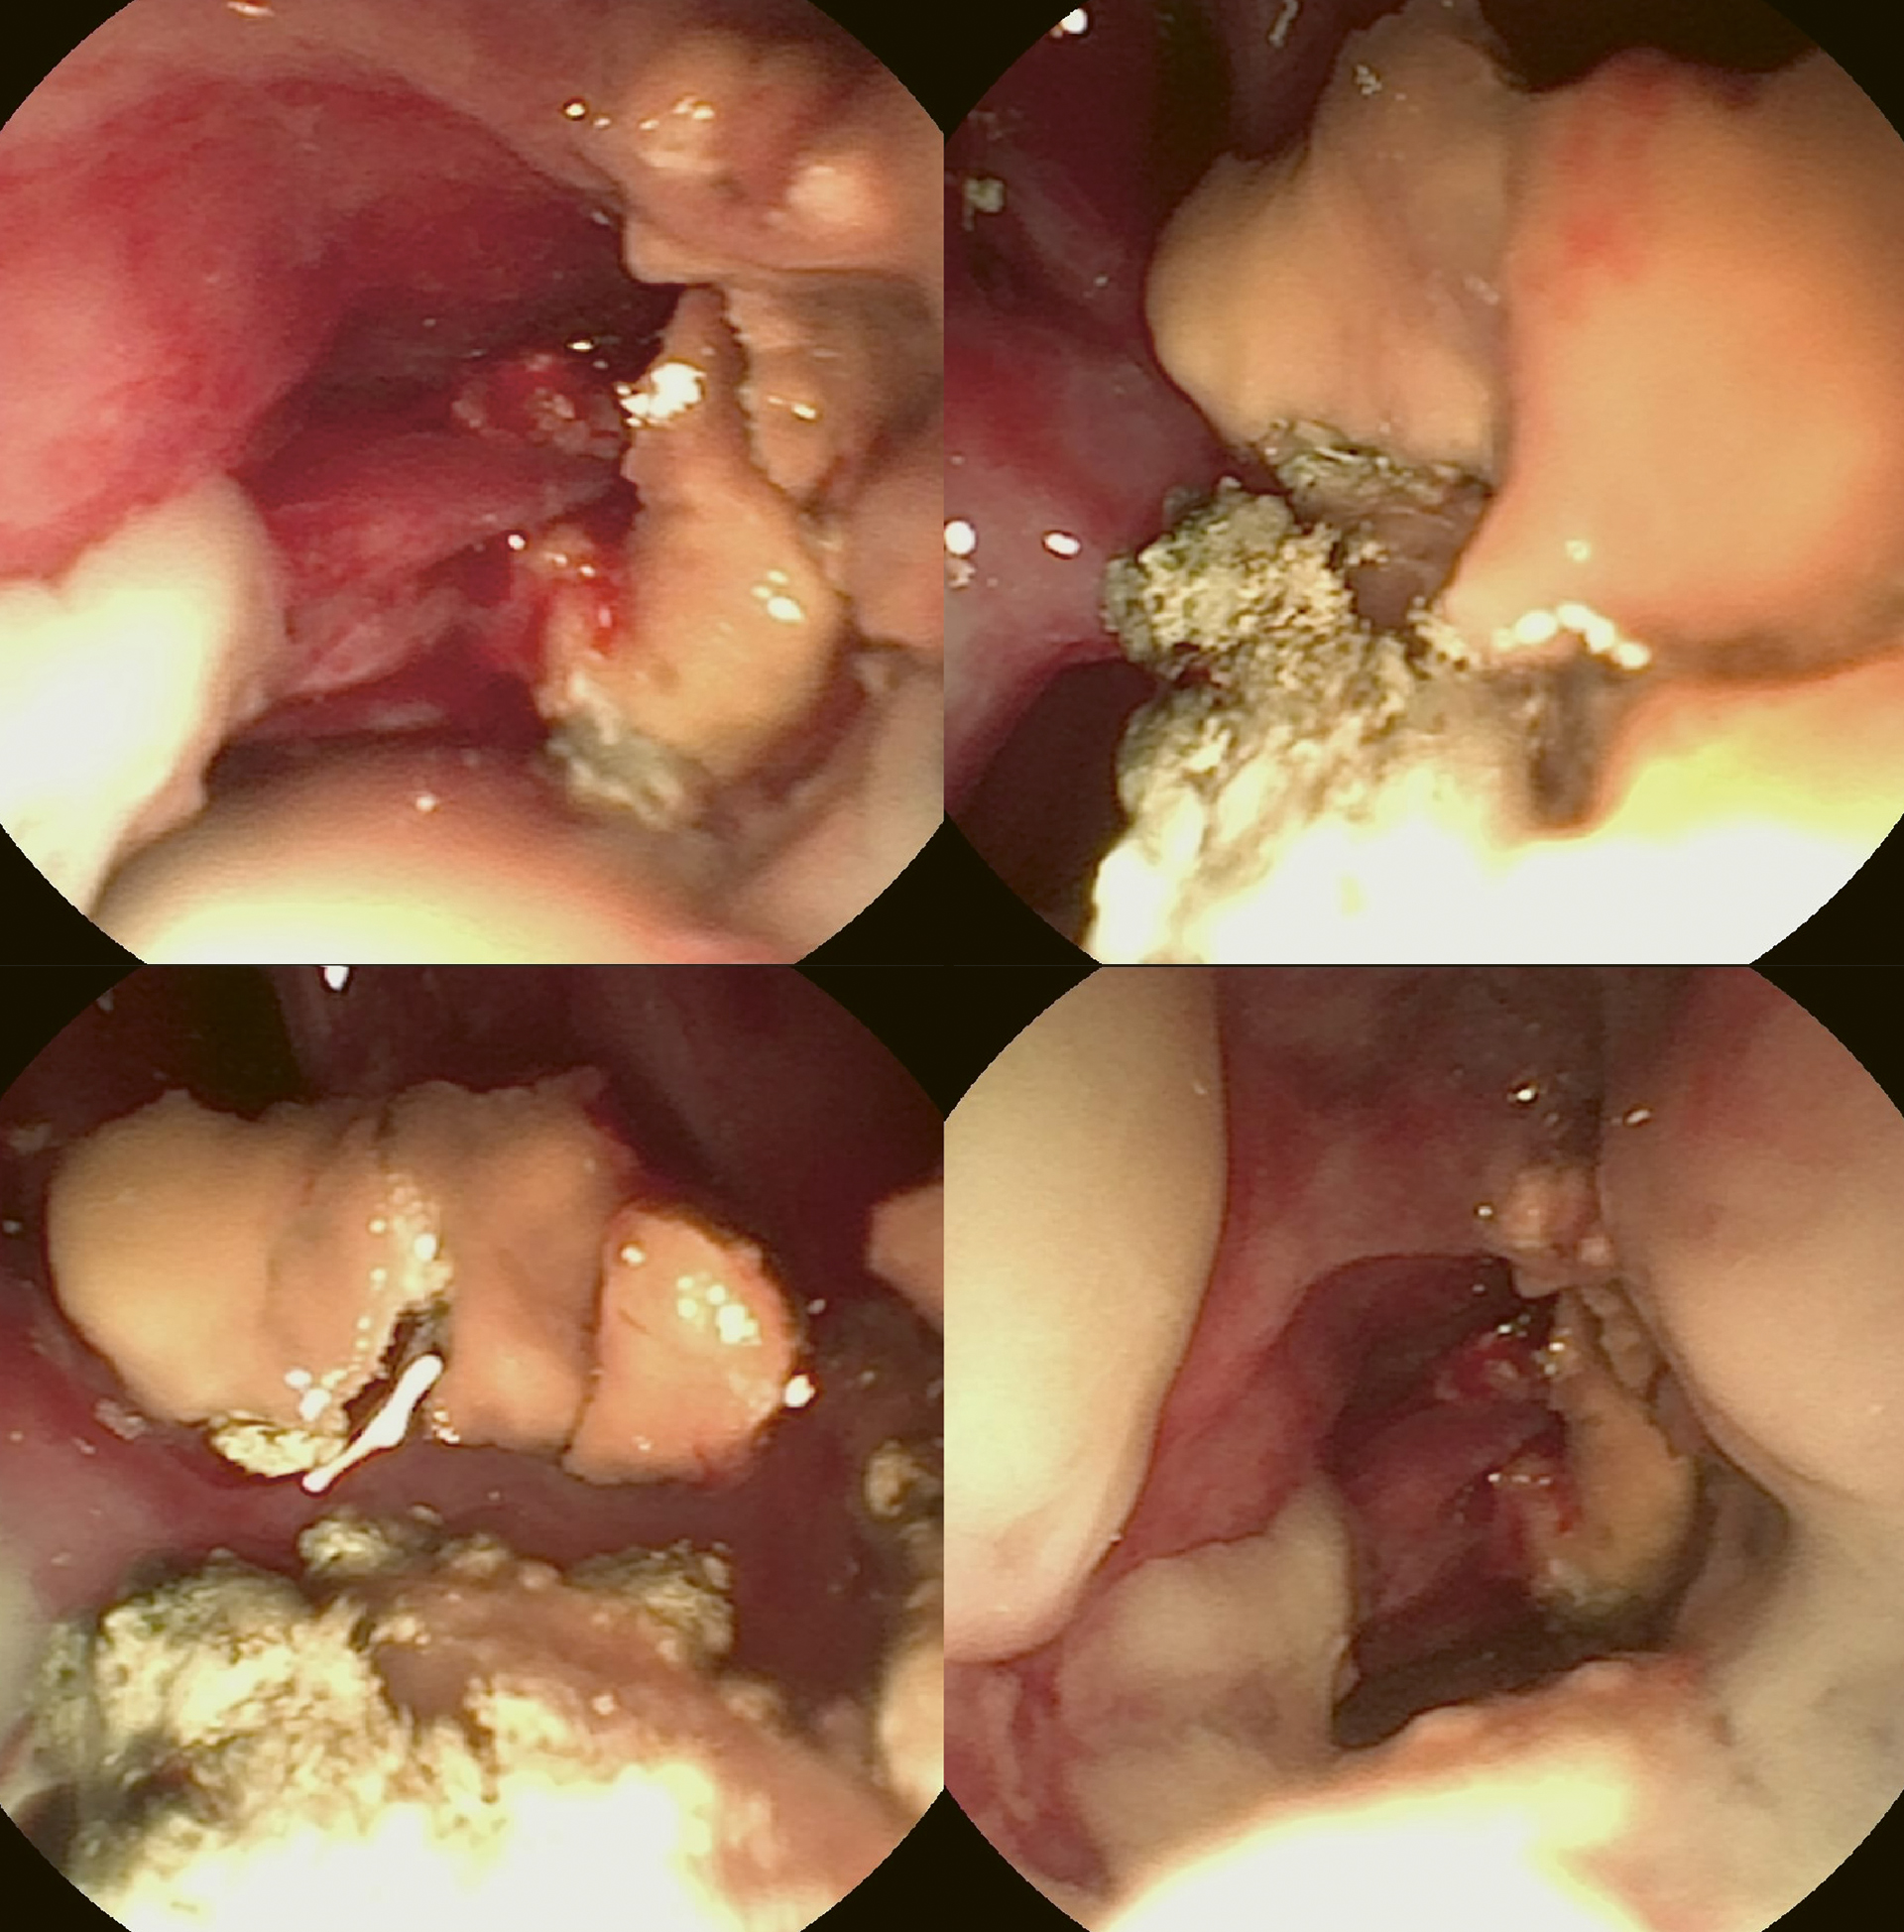

Figur 1. Rhinoskopiundersøkelse som viser nekrose, fragile slimhinner og gulhvite og grønnlige plakkformasjoner i høyre nesehule.

Foto: Caroline Solberg Graham

Larynx, pharynx og nasopharynx ble inspisert med et 3,5 mm fleksibelt Karl Storz engangs videoendoskop. Det kunne observeres mildt erytem over plica vocalis, rundt epiglottis og over et mindre område i nasopharynx. Svelget ble så pakket med kompresser før rhinoskopi ble utført. Rhinoskopiundersøkelsen ble utført med et 2,7 mm rigid Karl Storz Hopkins® Telescope 0° med hylse som hadde arbeidskanal og konstant vanntilførsel. Nesehulen ble inspisert systematisk fra ventrale nesegang, deretter over til midtre nesegang, og til slutt ble dorsale nesegang inspisert. Det ble observert gulhvite og grønnlige plakkformasjoner i midtre og ventrale nesegang bilateralt (Figur 1). Høyre halvdel av nesehulen var kraftig affisert, venstre halvdel var kun mildt affisert. Det ble i tillegg observert nekrose i høyre halvdel av nesehulen med fragilt vev som blødde og prellet vekk lett ved manipulering, samt små mengder pussdannelse. Slimhinnene var fragile og blødde lett ved manipulering bilateralt i nesehulen. Det ble plukket ut flere biter av plakket fra høyre halvdel av nesehulen ved hjelp av en gripetang. Vevsprøvene ble overført til EDTA-rør, flytende Amies mediumrør og i form av utstryk som ble sendt til analyse for mykologisk, bakteriologisk og cytologisk undersøkelse. Det ble laget et avtrykk av plakket fra nesehulen på et objektglass. Mikroskopisk undersøkelse av dette viste soppsporer (Figur 2).